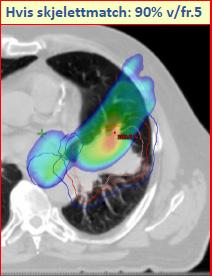

Tittelen for møtet i 2019 var Adaptiv strålebehandling - hvordan håndterer vi endringer underveis? Dette ble grundig belyst av foredragsholdere med bakgrunn som onkologer, fysikere og stråleterapeuter, fra Tromsø, Bergen, Trondheim og Oslo, i tillegg til Angela Baker, stråleterapeut fra Oxford i Storbritannia, og fysiker Ditte Sloth Møller fra Århus i Danmark. Programmet favnet vidt, med eksempler fra behandling av kreft i hode/hals, lunge, prostata og livmorhals, oppskrift på hvordan en adaptiv strateg kan implementeres, samt behov for adaptiv strategi ved protonbehandling. Det var endog et foredrag om maskinlæring, på et pedagogisk nivå som var lett til å forstå. som toksisiteten holdes uendret, eller reduseres. Det har skjedd en enorm utvikling av tekniske muligheter innen strålebehandling, både med hensyn til behandlingsteknikker og avbildingsmuligheter. «Gamle dager» med bare skjelettmatch utfra ortogonale megavolt eller kV (rtg) bilder er ikke så lenge siden, men føles nå for mange behandlingssituasjoner uansvarlig etter innføring av daglig cone beam CT på behandlingsapparatet og muligheten for bløtvevsmatch (figur 1).

Kan en del av behandlingssvikten vi ser ved for eksempel lungekreftbehandling være på grunn av suboptimal dosedekning som følge av endringer i målvolumets posisjon (figur 2)?